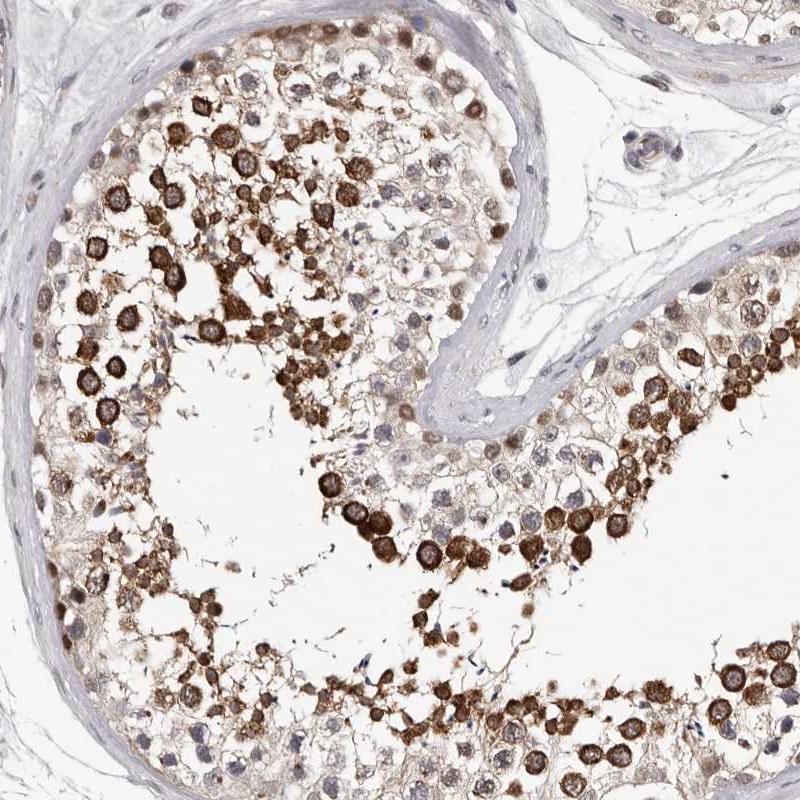

Immunohistochemistry analysis in human testis and pancreas tissues using Anti-RALGPS2 antibody. Corresponding RALGPS2 RNA-seq data are presented for the same tissues.